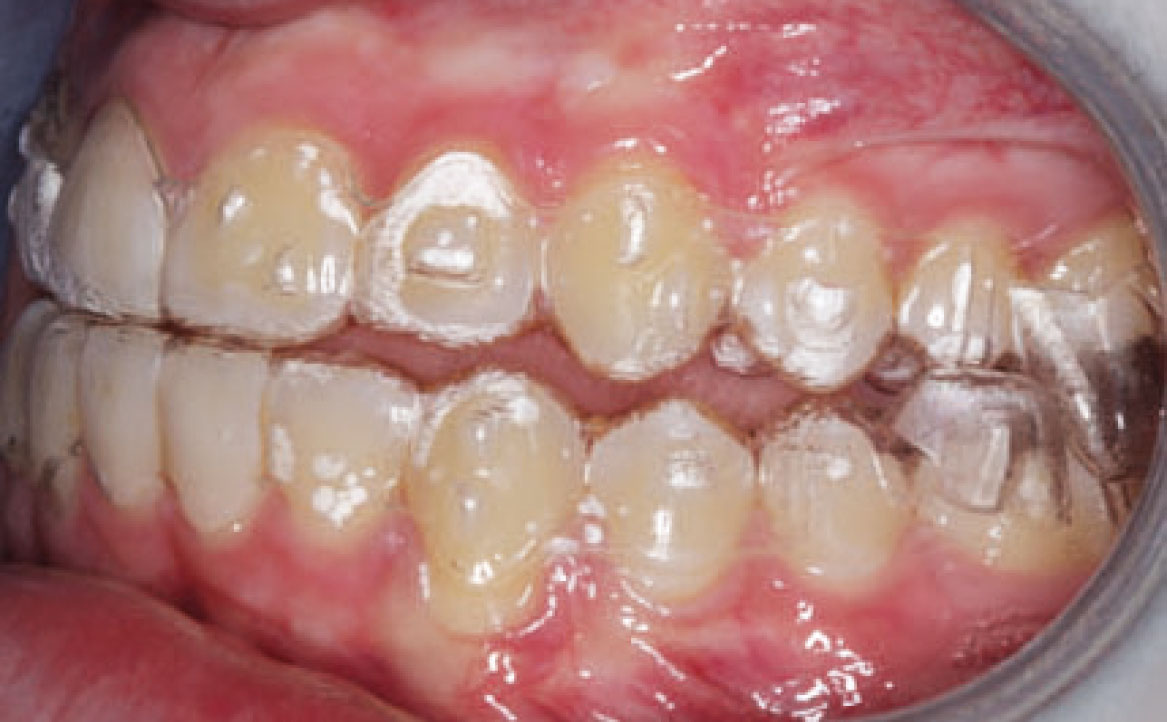

Dall’esame obiettivo intra orale si osservava una seconda classe canina destra e sinistra, una seconda classe molare destra e sinistra, e un diametro inter-canino e inter-molare ridotto sia in riferimento al mascellare superiore sia al mascellare inferiore (fig. 3A-3E).

A seguito del trattamento è stato osservato un miglioramento dell’igiene orale (fig. 5).

In seguito alla rivalutazione, al fine di ottimizzare il rapporto sagitale, è stata pianificata la seconda fase del trattamento, la quale aveva previsto l’utilizzato di allineatori trasparenti con il sistema Invisalign® con protocollo MA (fig. 7).

In seguito, il paziente è stato monitorato periodicamente sia dal reparto di ortodonzia che dal reparto di igiene orale a causa della sua storia clinica di cariorecettività inziale (fig. 8, 9).